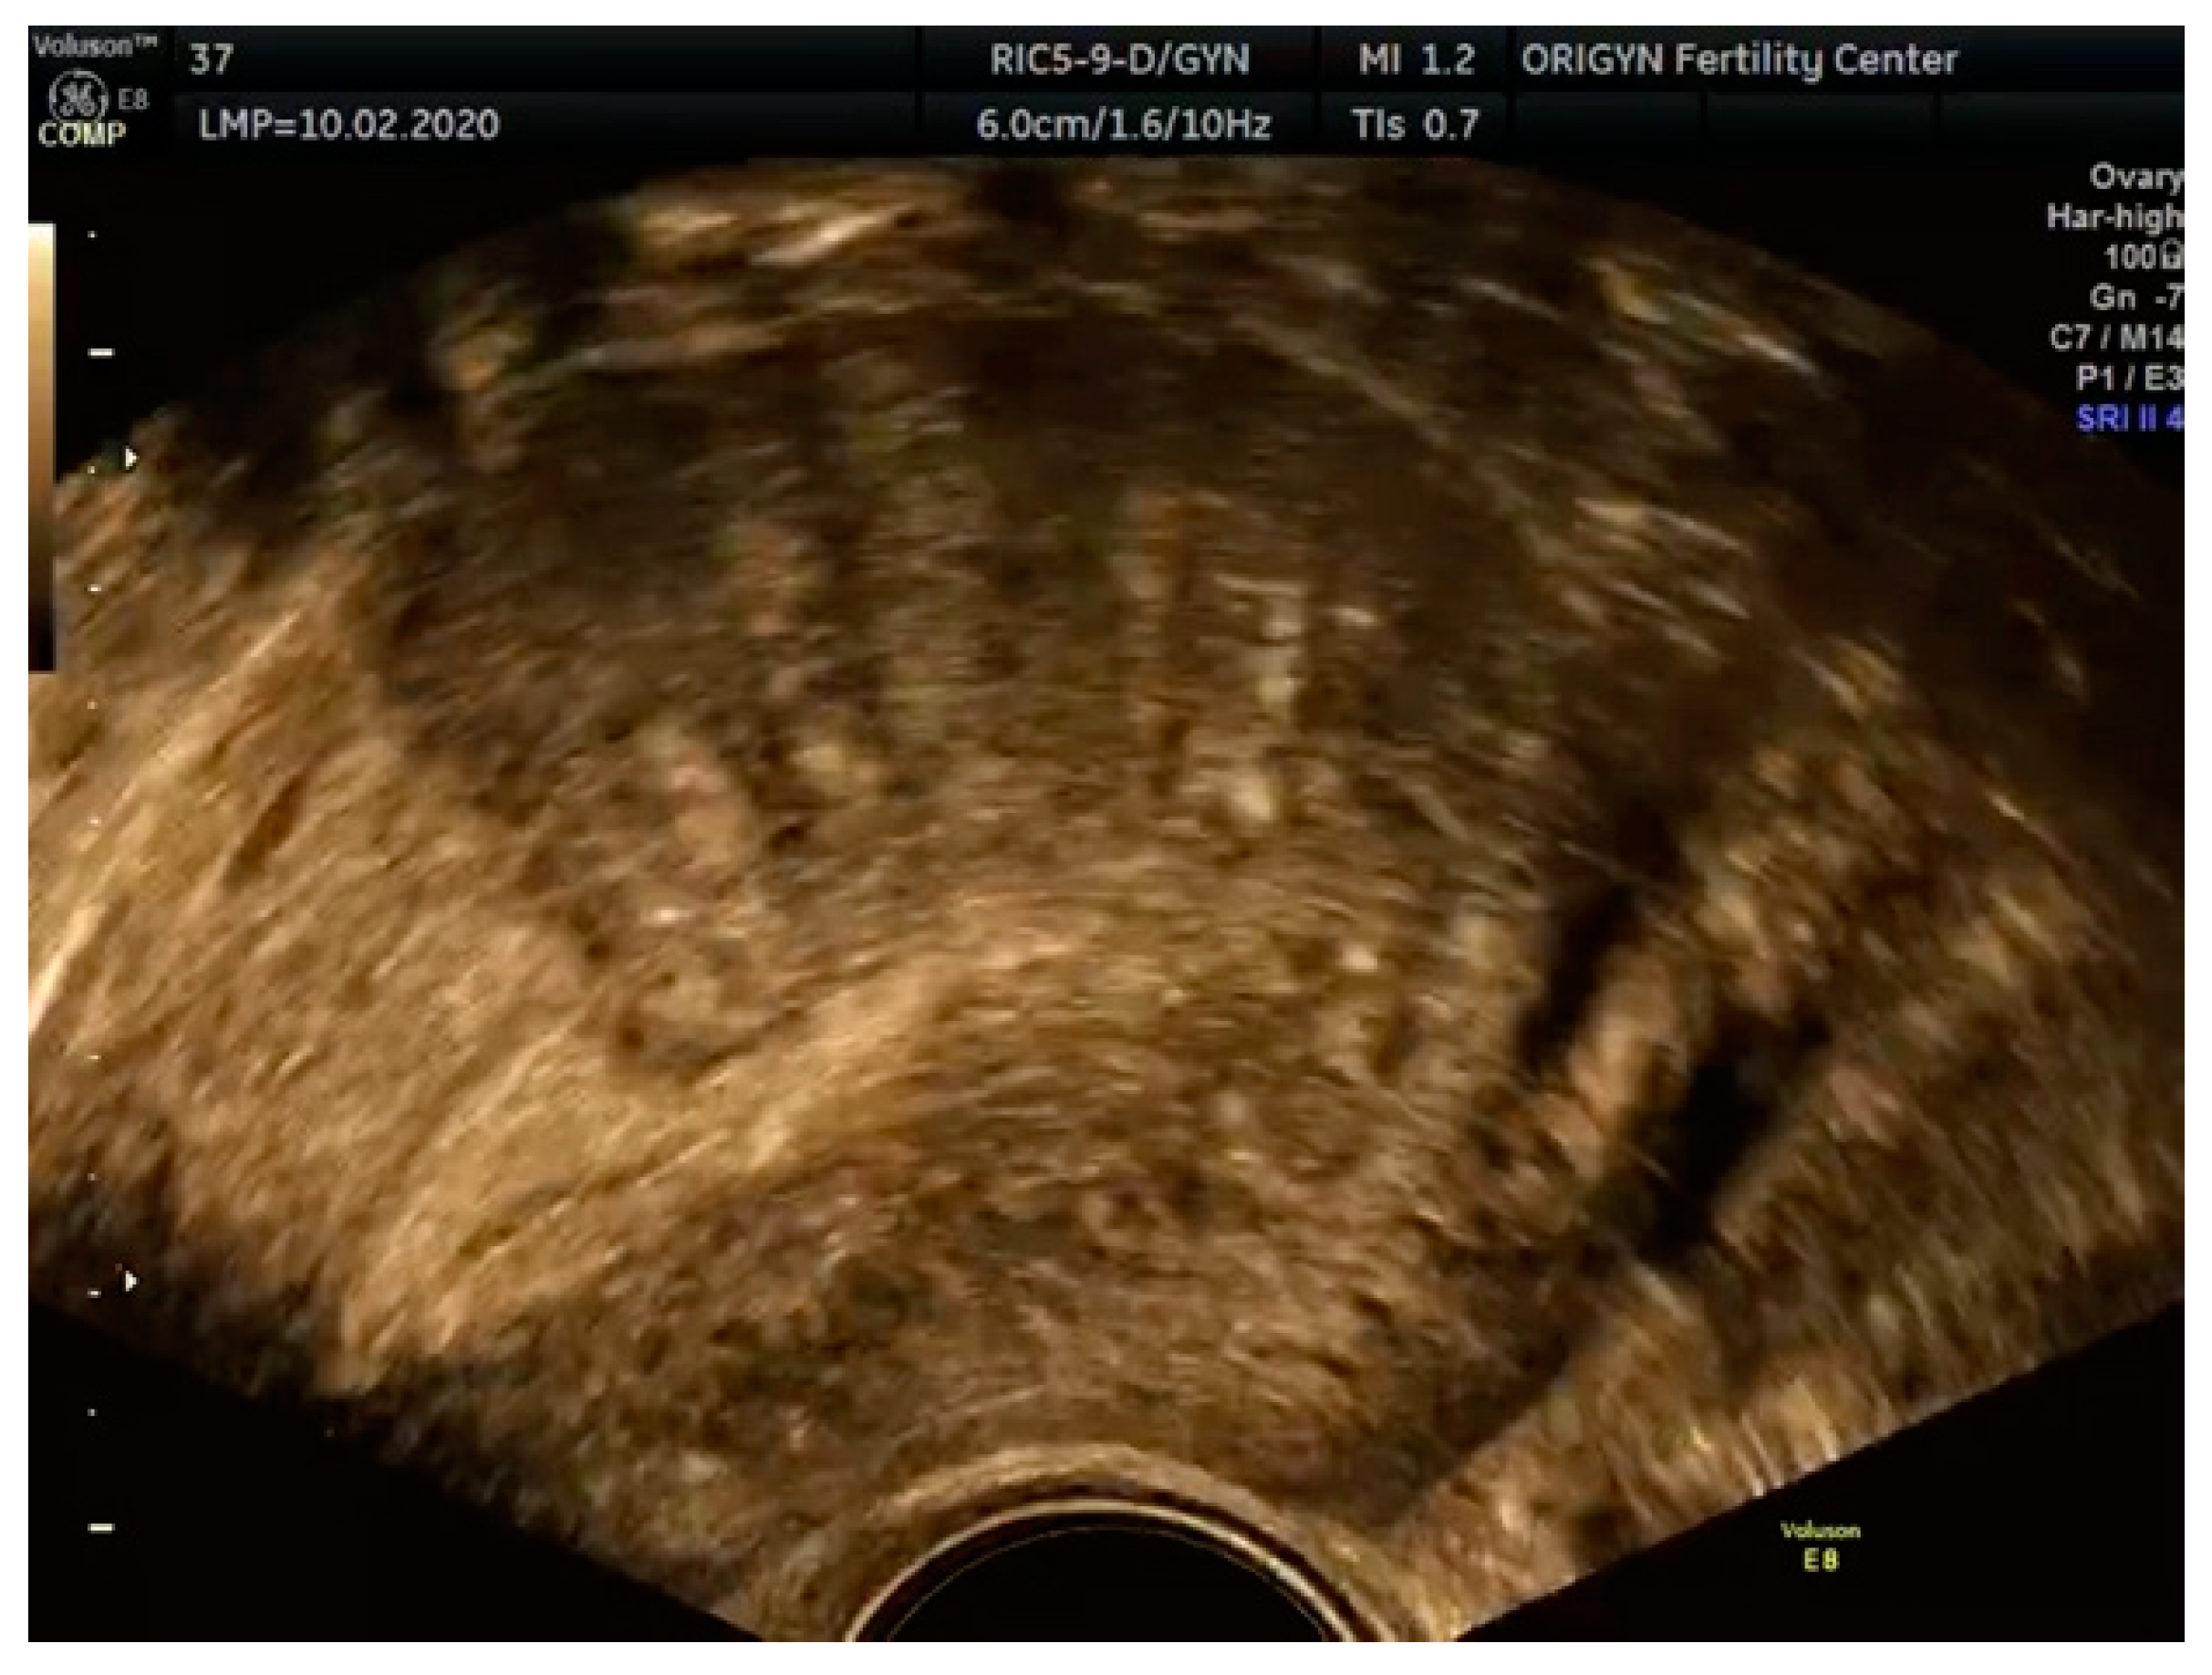

3.1. ADNEXA

3.2. Adenomyosis